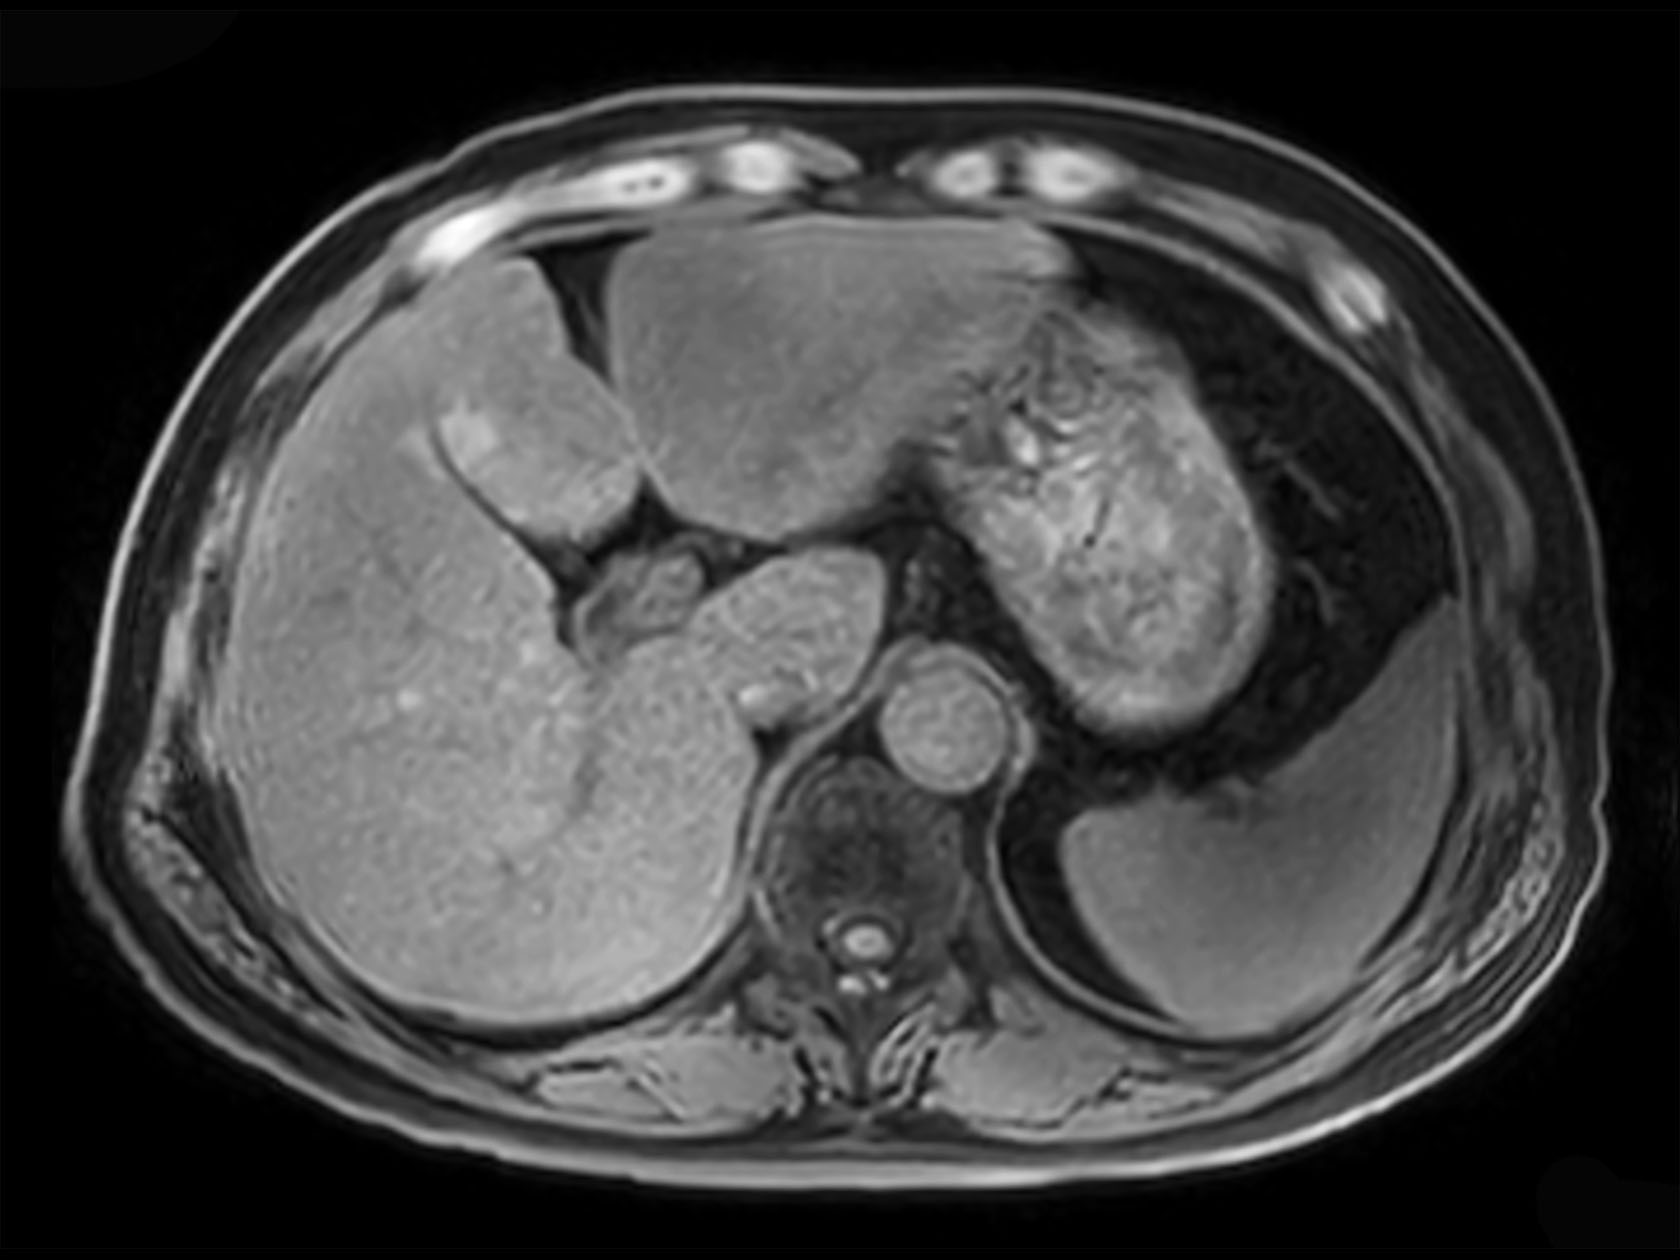

Axial 3D VANE XD (Out Phase)